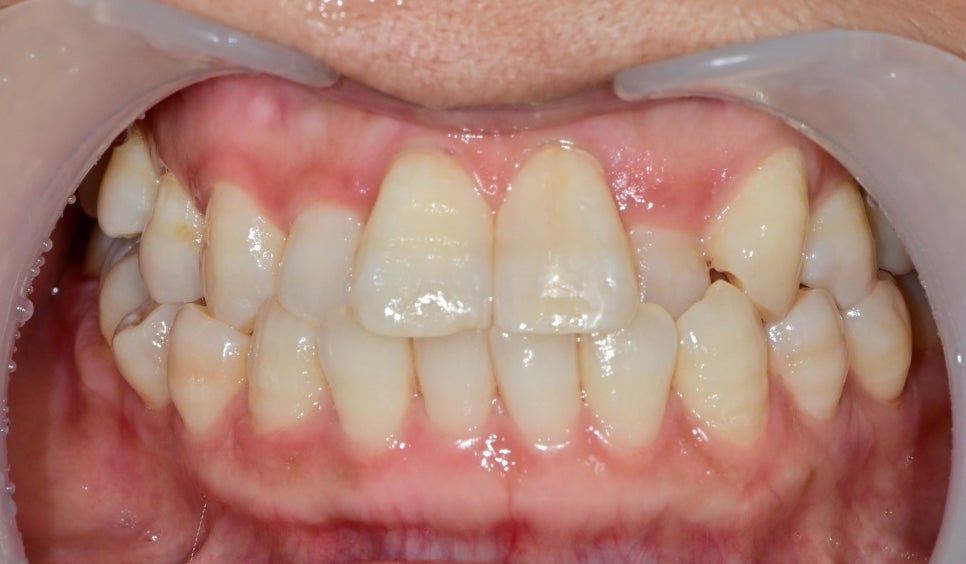

크랙 부위만 살짝 다듬어 내어 레진을 이용하여

크랙 라인을 덮어보는 치료를 했습니다.

치료 후 밝게 하여 찍은 사진입니다.

크랙 라인을 가리기 위해 레진 색이 살짝 보이긴 하지만

전과 비교하여 훨씬 자연스러운 색과 형태를 볼 수 있습니다.

심미치료는 각자 치아 컨디션이나 상황에 따라

환자분과 같이 고민하고 알맞은 치료를 선택할 수도 있습니다.